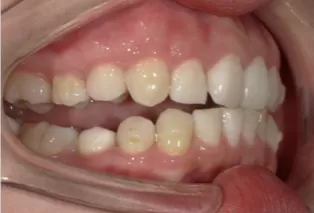

Photos intra-orales